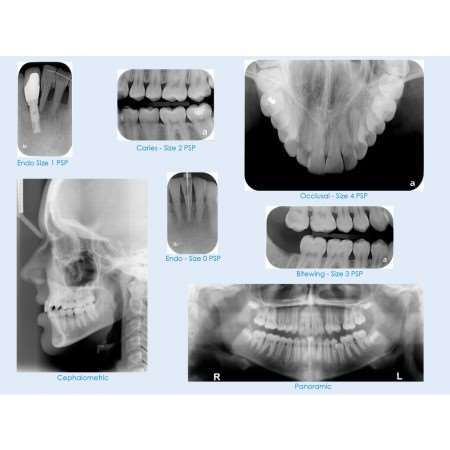

IntraOral Phosphor Imaging Plates Size 0 2/pk. - MARK3®*

IntraOral Phosphor Imaging Plates Size 0 2/pk. - MARK3®*